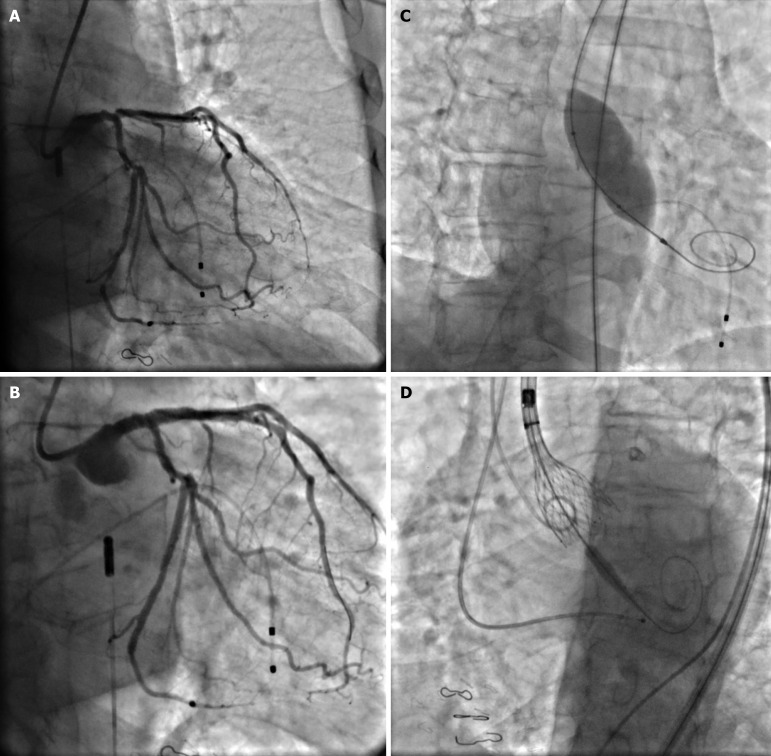

Case summary: An 82-year-old man presented with dyspnea on exertion. Echocardiogram was significant for severe aortic stenosis. Following a heart team discussion, the patient was scheduled for a balloon valvuloplasty followed by staged TAVR. Based on pre-TAVR computed tomography angiogram, the aortobifemoral graft was deemed as an appropriate access site. Micropuncture needle was used to access the right femoral artery graft, and the sheath was upscaled to 10 Fr. He underwent successful intervention to ostial left anterior descending and left circumflex arteries, and BAV with 22 mm Vida BAV balloon. Hemostasis was achieved using Perclose. For TAVR, an 8 Fr sheath was inserted via the right femoral bypass graft. The arteriotomy was pre-closed with two Perclose ProGlides and access was upsized to 18F Gore DrySeal. A 5Fr sheath was used for left femoral bypass graft access. Patient underwent successful TAVR with 29 mm CoreValve. Hemostasis was successfully achieved using 2 Perclose for right access site and one Perclose for left side with no postoperative bleeding complications.